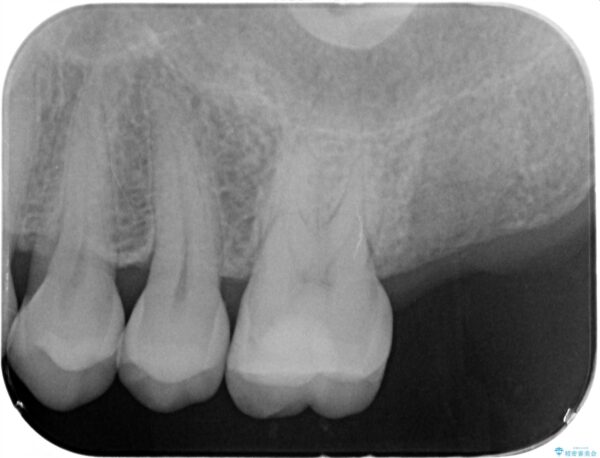

治療前

【噛むと歯が疼く】歯牙破折からのインプラント治療 治療前画像 【噛むと歯が疼く】歯牙破折からのインプラント治療 治療前画像 【噛むと歯が疼く】歯牙破折からのインプラント治療 治療前画像 【噛むと歯が疼く】歯牙破折からのインプラント治療 治療前画像 【噛むと歯が疼く】歯牙破折からのインプラント治療 治療前画像 【噛むと歯が疼く】歯牙破折からのインプラント治療 治療前画像 【噛むと歯が疼く】歯牙破折からのインプラント治療 治療前画像